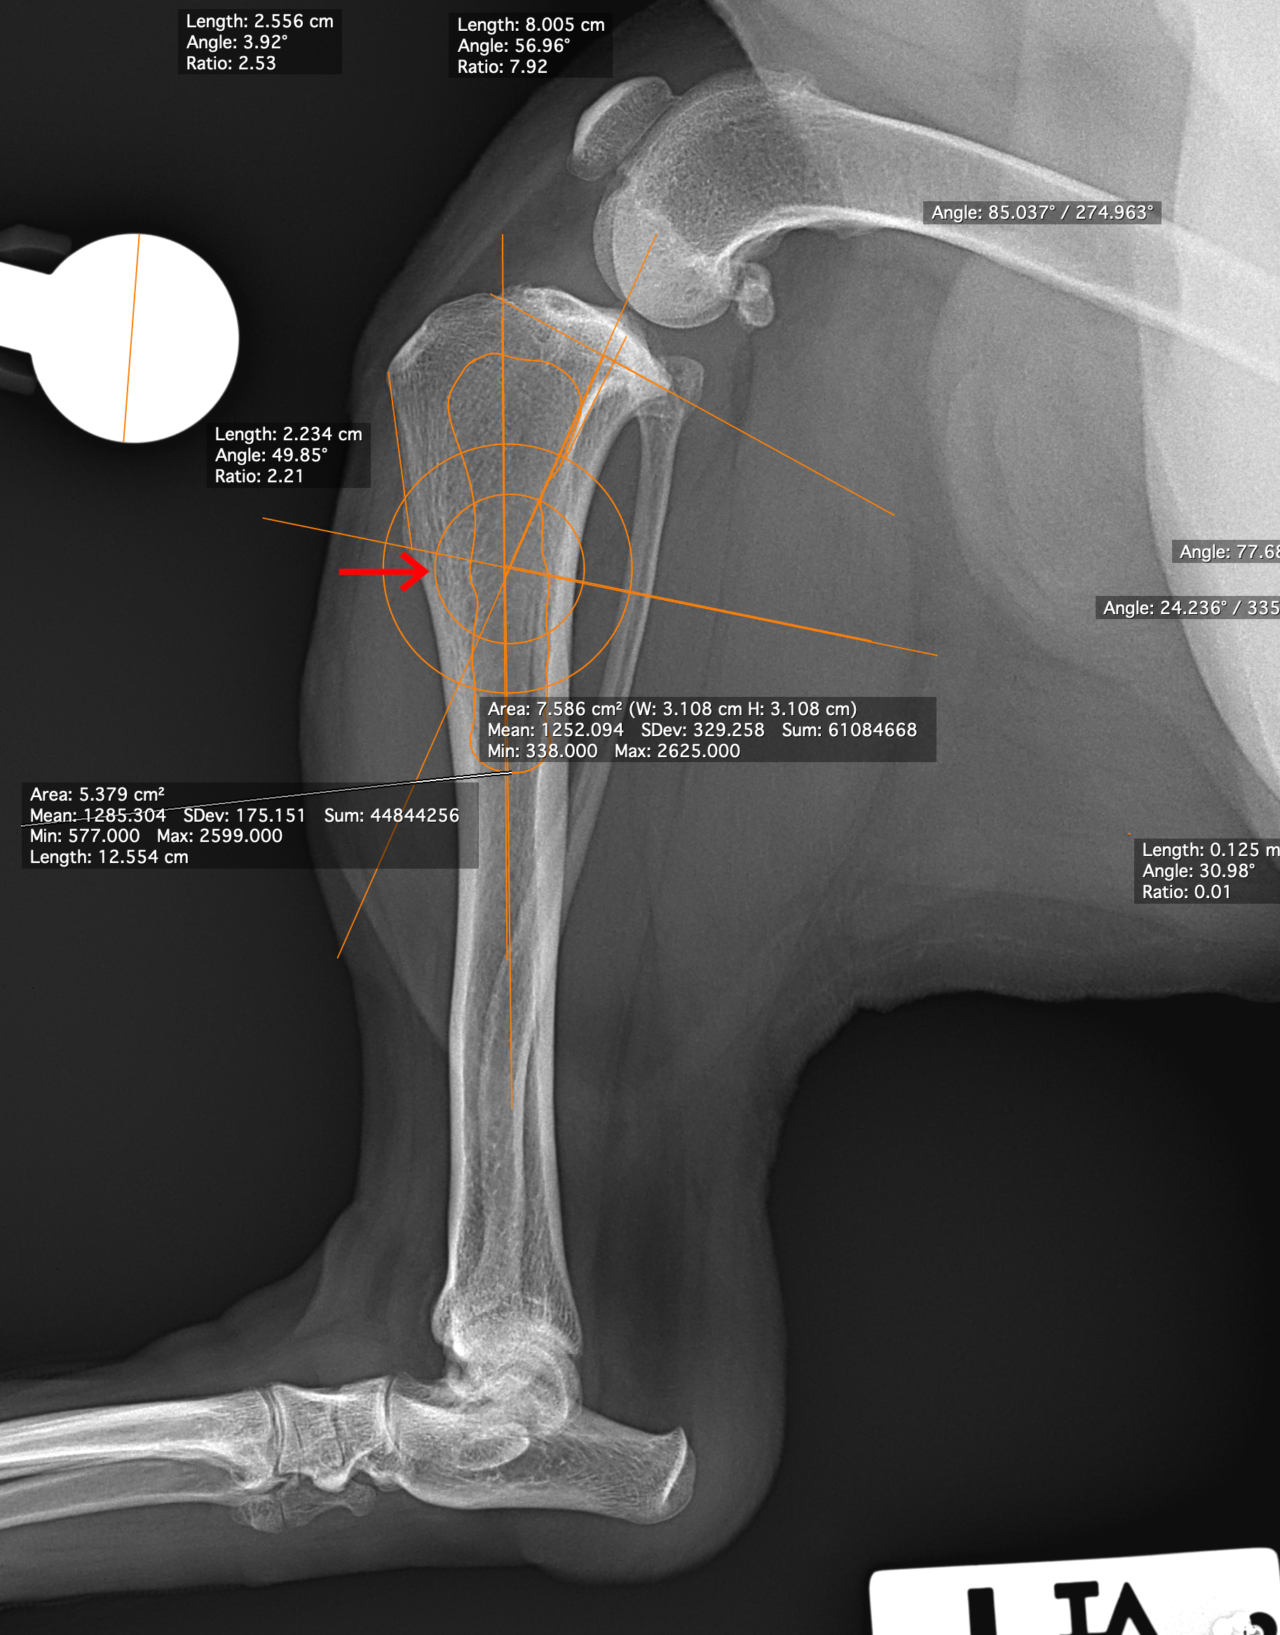

CBLO #248

性の前十字靭帯断裂の中型犬にCBLOで安定化を実施しました。慢性経過のためミディアルバトレスが分厚くなって触知することが可能です。また関節内を探査すると、内側半月板の尾側領域はダブルバケットハンドルという状態で亀裂が2ヶ所確認されました。しばらくは安静が必要です。